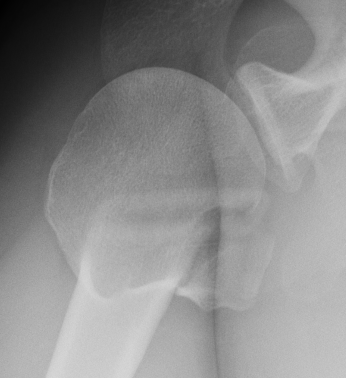

AP Xray

Abnormal overlap of humeral head on glenoid

Light-bulb sign - globular head secondary to internal rotation of the humeral head

Vacant Glenoid Cavity - > 6 mm space between humeral head and anterior rim of glenoid

Axillary Xray

Diagnostic - humeral head posterior to glenoid with evidence of reverse Hill Sachs

Reverse Hill Sachs

Humeral head defect

- caused by impaction of anterior humeral head on posterior glenoid

- intra-articular

- measured as a percentage of the articular surface